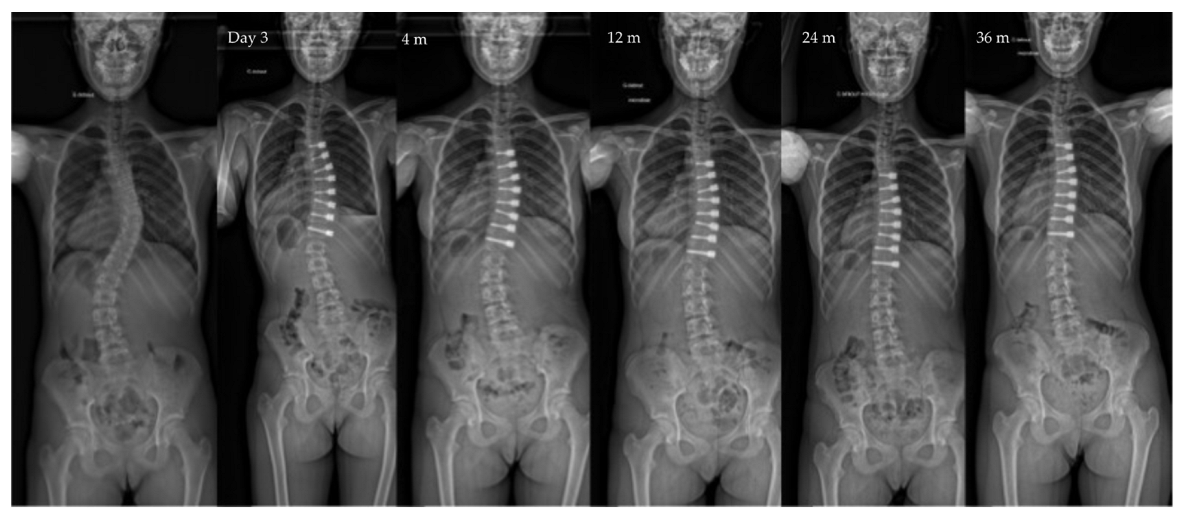

| Pre-op | Post-op Day 3 | Post-op 1y | Last f/u | p-Value | |

|---|---|---|---|---|---|

| Major curve | 49°(8,9°) | 27°(12°) | 22°(12°) | 19°(14°) | <0.01 |

| Secondary curve | 27°(14°) | 23°(15°) | 22°(11°) | 17°(10°) | <0.01 |

| Instrumented curve | NA | 26°(11°) | 23°(10°) | 20°(14°) | <0.01 |

| Kyphosis (T1–T12) | 20°(13°) | 23°(13°) | 25°(12°) | 24°(14°) | 0.06 |

| Lordosis (L1–L5) | 36°(12°) | 32°(13°) | 40°(7°) | 40°(8°) | 0.07 |

| Overcorrection | 10 (11%) | 10 right thor. | 5 tether release | Between 1,5, and 2 y po |